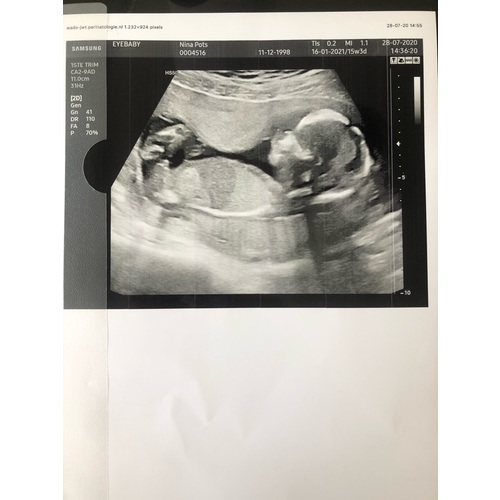

Voor een goede geslachtsbepalings echo word geadviseerd te wachten tot 15-16 weken. Omdat daarvoor de geslachtsorganen nog te veel op elkaar lijken.

Dus de kans is heel groot dat je gynaecoloog het kan zien. 🙂 Liefs

Bij ons zag je het met 14+5 overrduidelijk.zelfs ik zag het. Bij de 20-weken echo klopte het nog steeds :-)